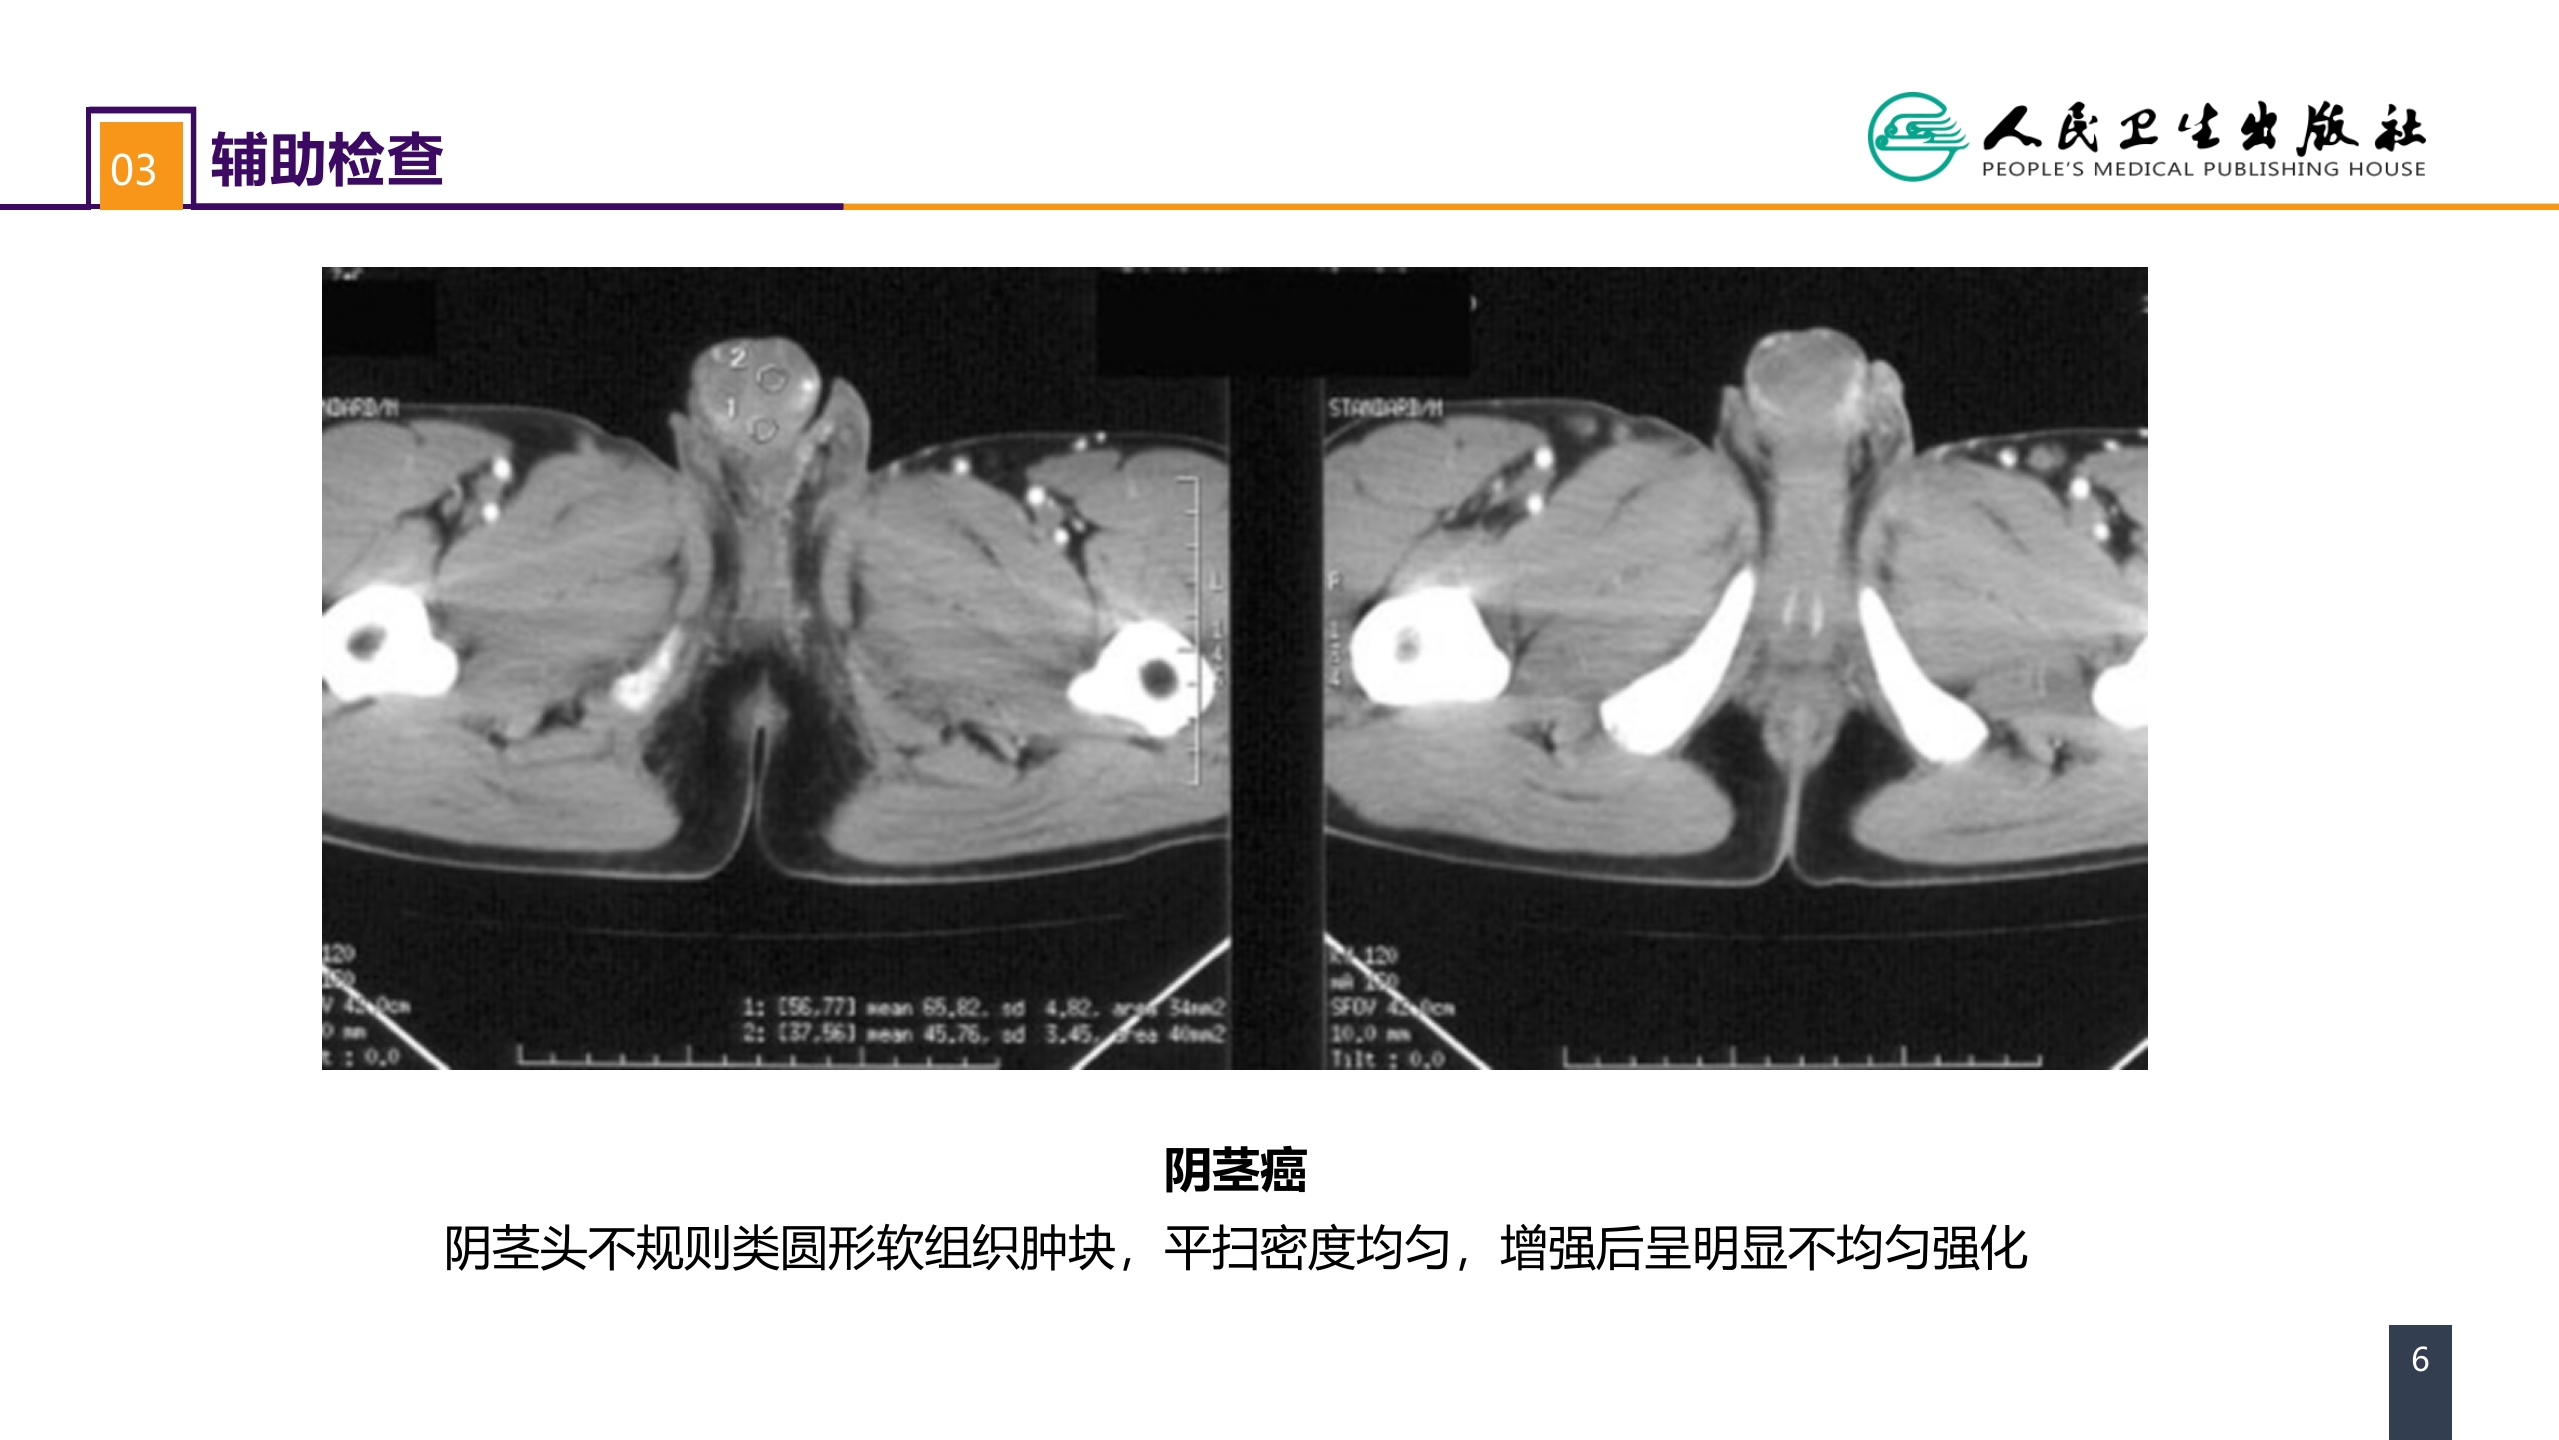

第五十三章 泌尿、男生殖系统肿瘤 案例分析-阴茎癌